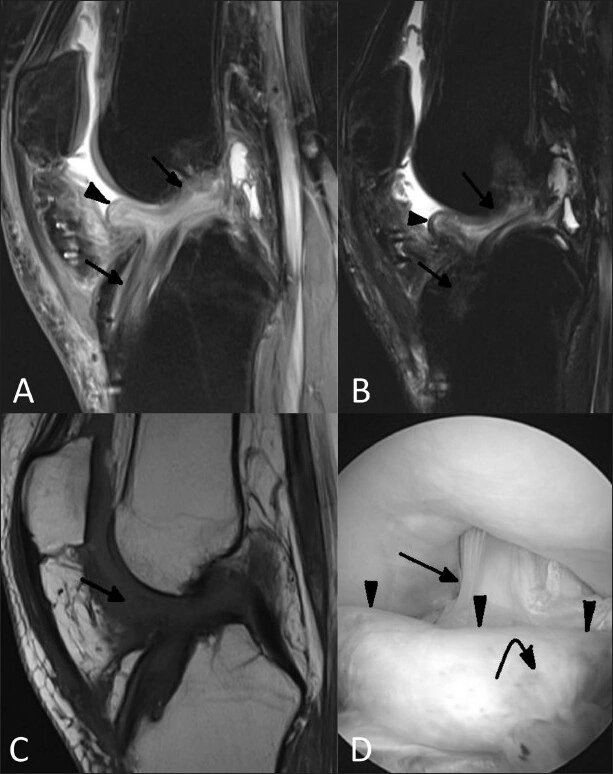

МРТ также позволяет определить положение большеберцового канала и выявить наличие рубцовой ткани кпереди от ПКС, которая обычно имеет низкую интенсивность сигнала.

При артроскопической ревизии межмыщелкового пространства обнаруживаются узелки рубцовой ткани разных размеров. При попеременном сгибании и разгибании видно, как рубцовая ткань собирается между мыщелками бедренной и большеберцовой костей, создавая препятствие для полного разгибания. Для рубцовой ткани характерна волокнистая структура, что требует дифференциации от волокон трансплантата.